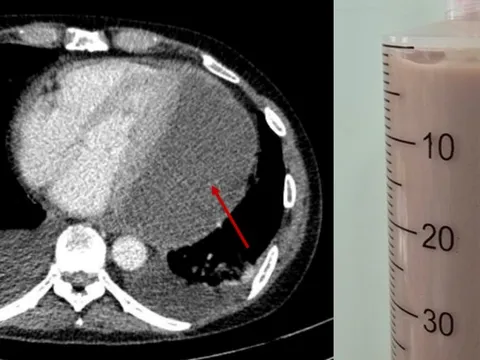

TPO - Sau khi ăn nhầm con so biển có độc tố thần kinh cực mạnh, người đàn ông 52 tuổi rơi vào nguy kịch. Nhờ kỹ thuật lọc máu hấp phụ độc chất, các bác sĩ Bệnh viện Nhân dân 115 đã kịp thời cứu sống bệnh nhân trong gang tấc.